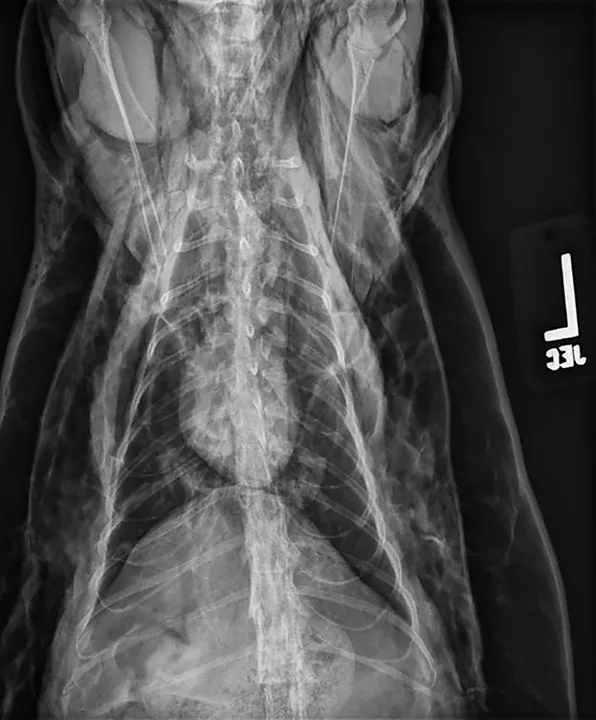

Ventrodorsal view of a patient with severe pneumomediastinum and severe subcutaneous emphysema secondary to a tracheal tear

A pneumomediastinum diagnosis is made via thoracic radiography (Figures 1 and 2). Air in the mediastinum outlines the cranial vena cava, dorsal and ventral tracheal walls, esophagus, and aorta. Gas may be present in the retroperitoneal space, cervical fascial planes, and subcutaneous space.2 If an obvious cause of pneumomediastinum is not apparent and the patient is stable, an oropharyngeal examination may be performed with the patient under sedation. Fluoroscopy with iodinated water-soluble contrast or endoscopy can be used to evaluate for esophageal lesions. Airway integrity may be assessed via endoscopy, although small lesions in the trachea may be missed. Advanced imaging (eg, CT) can be helpful in identifying the underlying lesion.